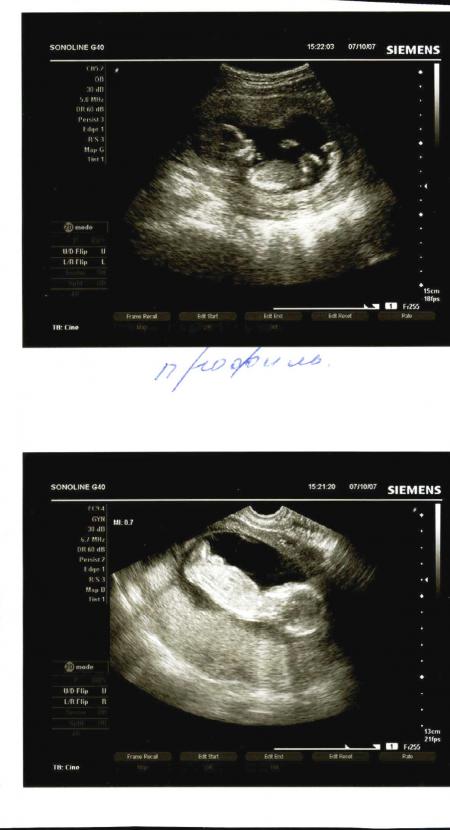

Девочки, сегодня на УЗИ ходила :))) Увидела своего малышика наконец-то!!! :))) Такой хорошенький....ПАльчики шевелились, сам тоже, сердечко слышала....:)))) Вобщем я в восторге....ак долго ждала этого...И вот!!!! А еще оказалось, что нам не 12, а 13 неделек!!!!

На скане профиль и со спинки вид)))) Нам еще отдельно сделали распечатку ручек))) И вид анфас)))